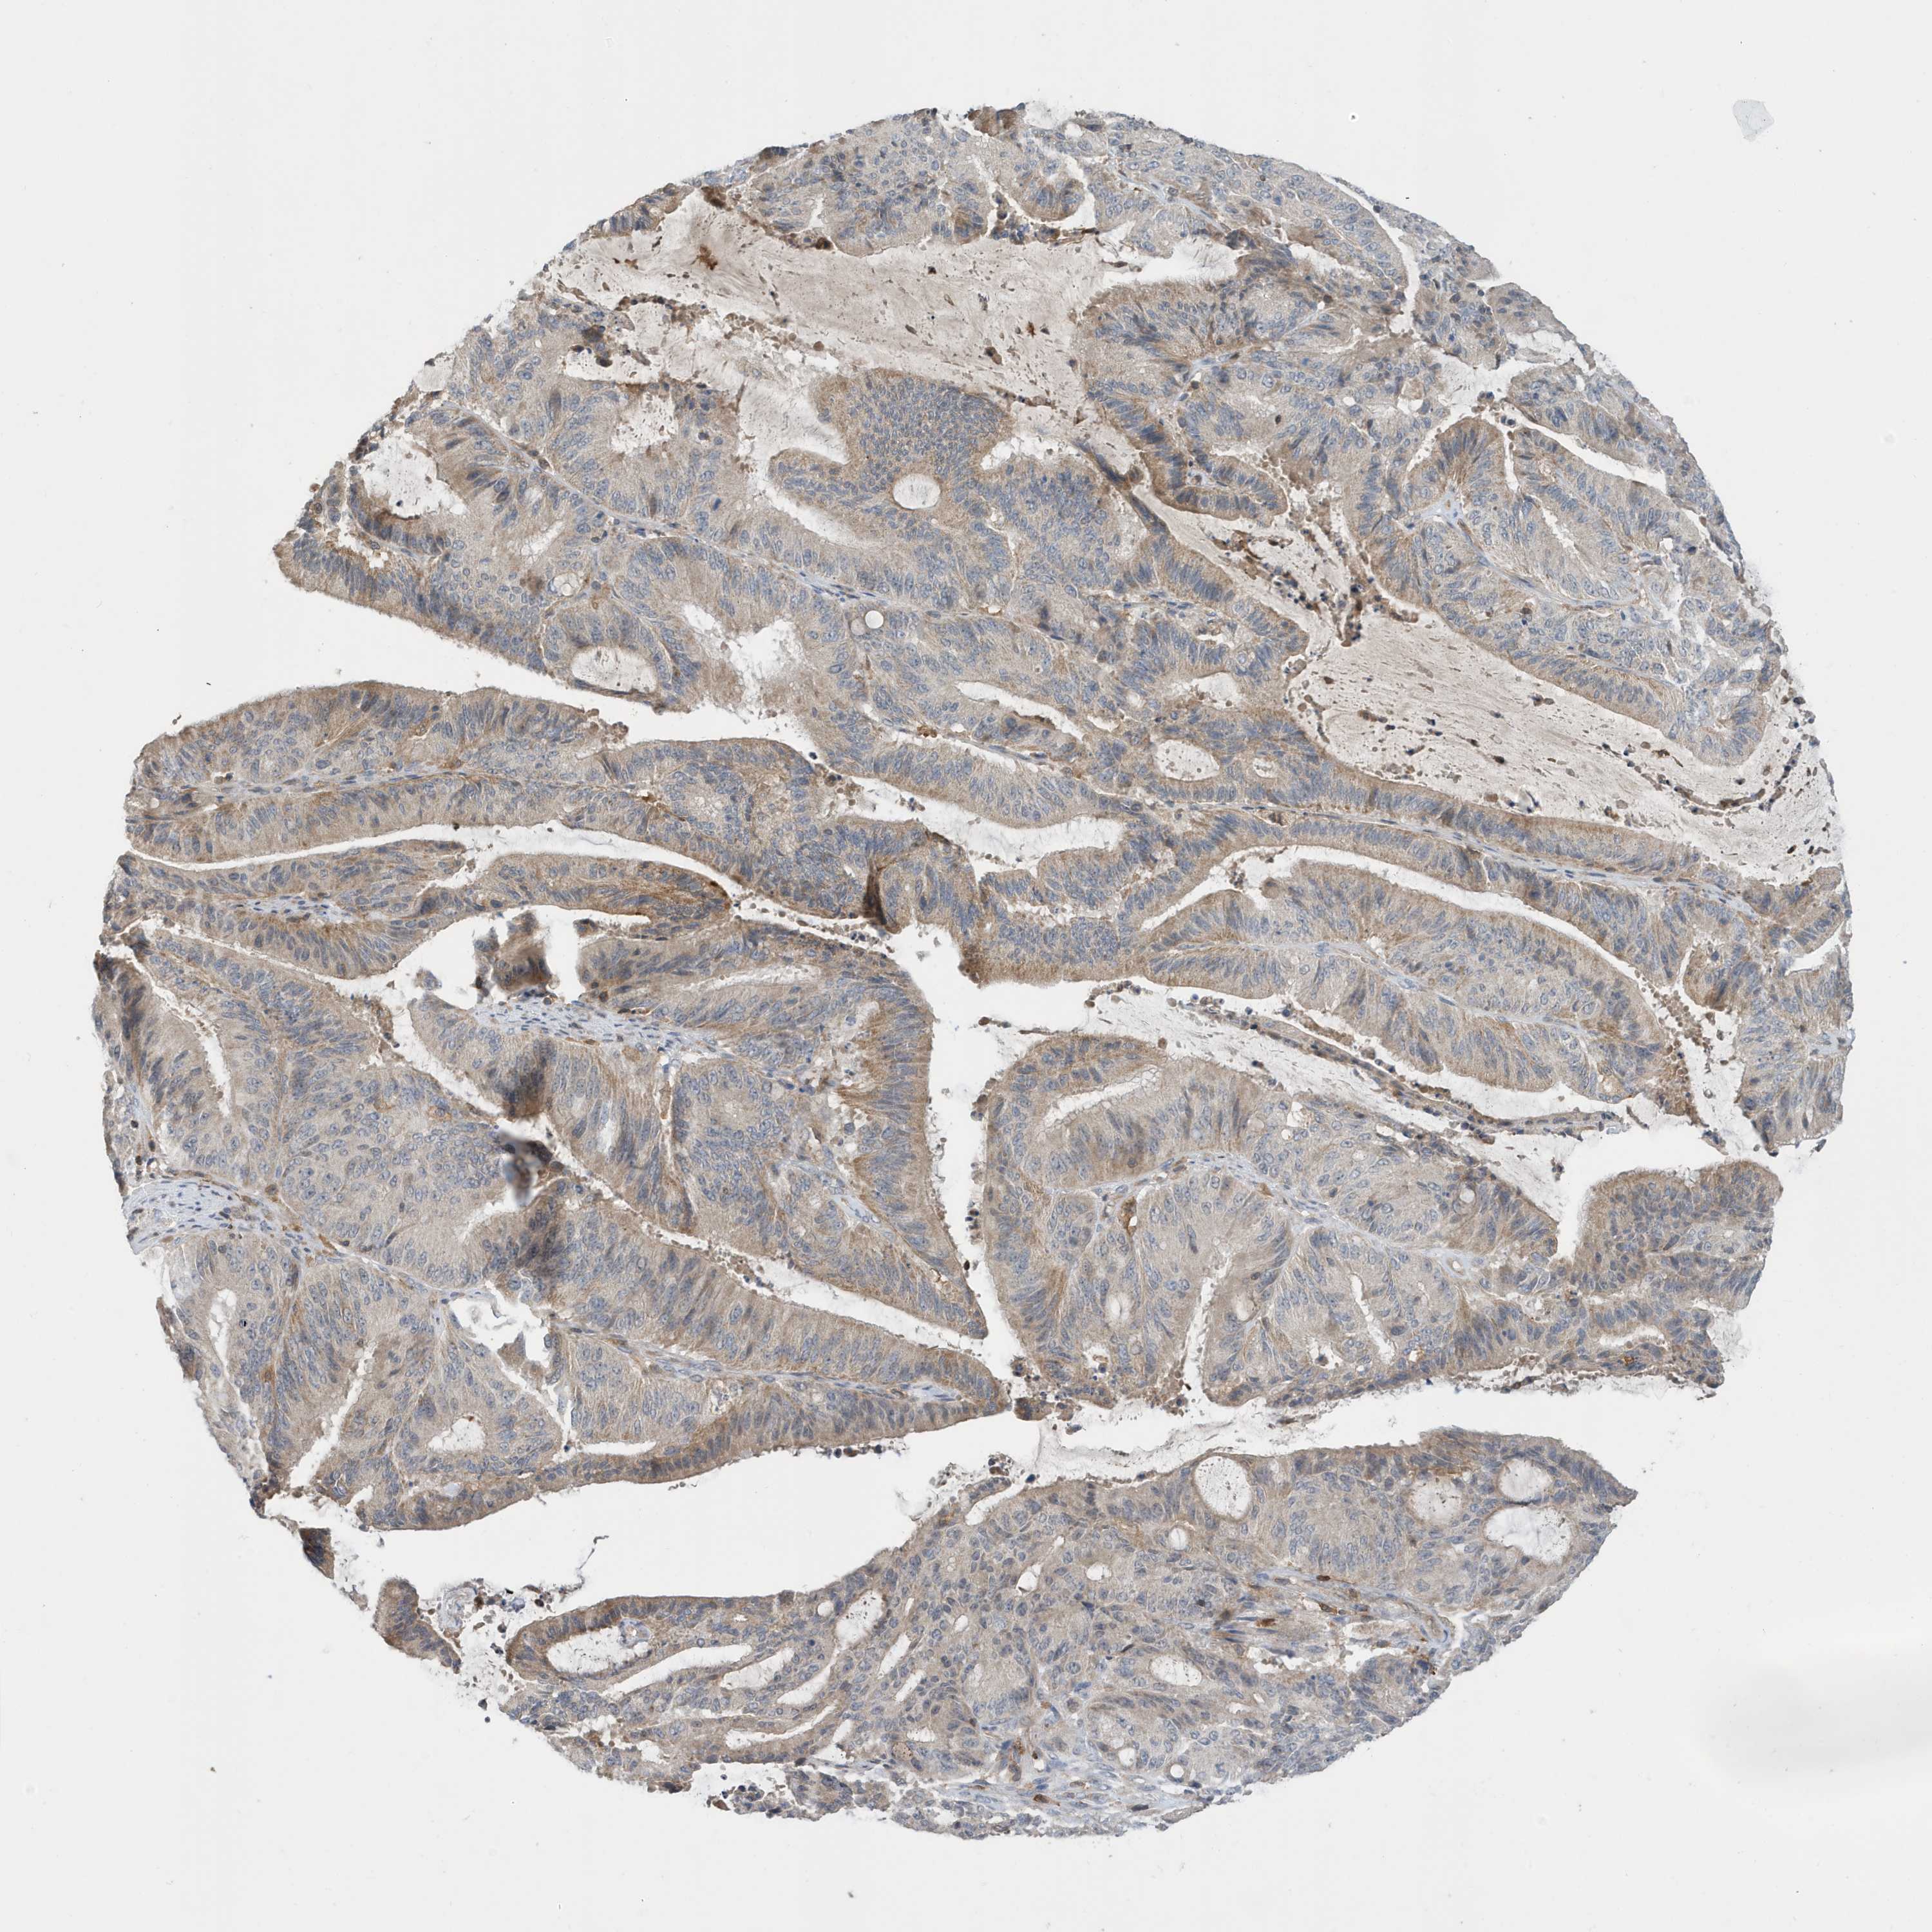

LIVER CANCER - Protein expressioni

A mouse-over function shows sample information and annotation data. Click on an image to view it in a full screen mode. Samples can be filtered based on level of antibody staining by selecting one or several of the following categories: high, medium, low and not detected. The assay and annotation is described here.

Note that samples used for immunohistochemistry by the Human Protein Atlas do not correspond to samples in the TCGA dataset.

Antibody stainingi

Antibody staining in the annotated cell types in the current human tissue is reported as not detected, low, medium, or high, based on conventional immunohistochemistry profiling in selected tissues. This score is based on the combination of the staining intensity and fraction of stained cells.

Each image is clickable and will lead to virtual microscopy that enables deeper exploration of all samples and also displays staining intensity scores, fraction scores and subcellular localization as well as patient and tissue information for each sample.

Antibody HPA036181

Staining

High

Medium

Low

Not detected

Intensity

Strong

Moderate

Weak

Negative

Quantity

>75%

75%-25%

<25%

None

Location

Nuclear

Cytoplasmic/membranous

Cytoplasmic/membranous,nuclear

Cholangiocarcinoma

Carcinoma, Hepatocellular, NOS